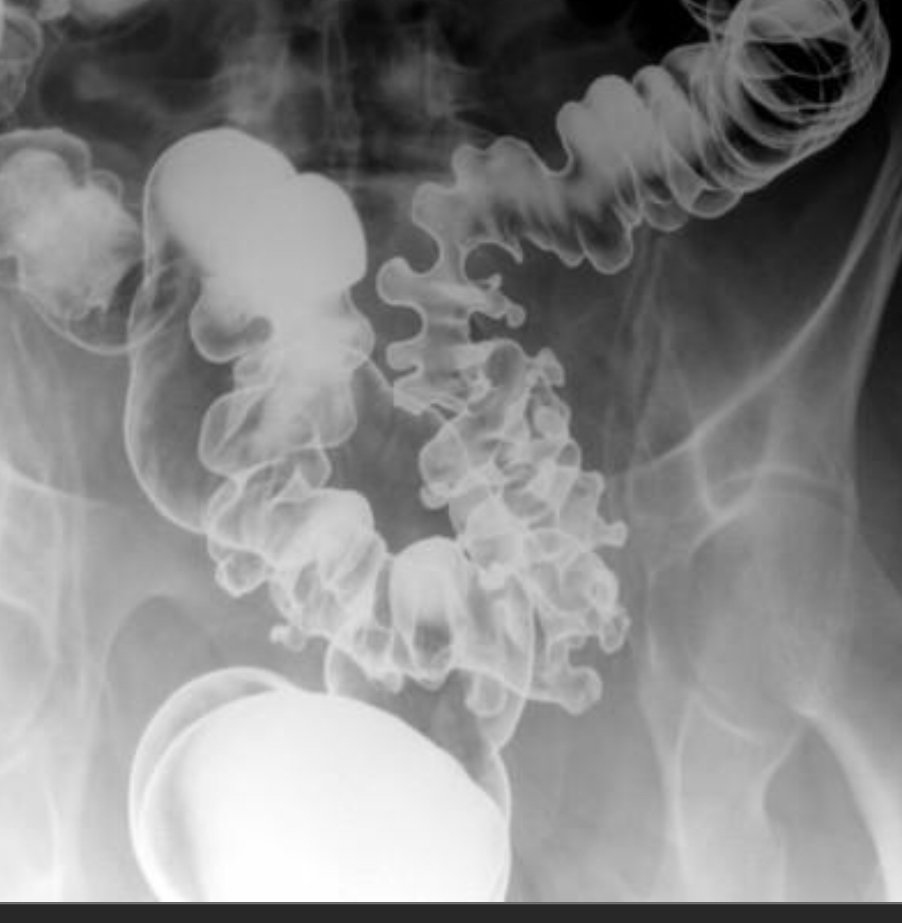

Middle aged man c/o intermittent crampy abdominal pain and constipation

Diverticulosis w/concentric/circular muscular hypertrophy

—Also known as myochosis

get ‘cogwheel’ narrowing of the colonic lumen